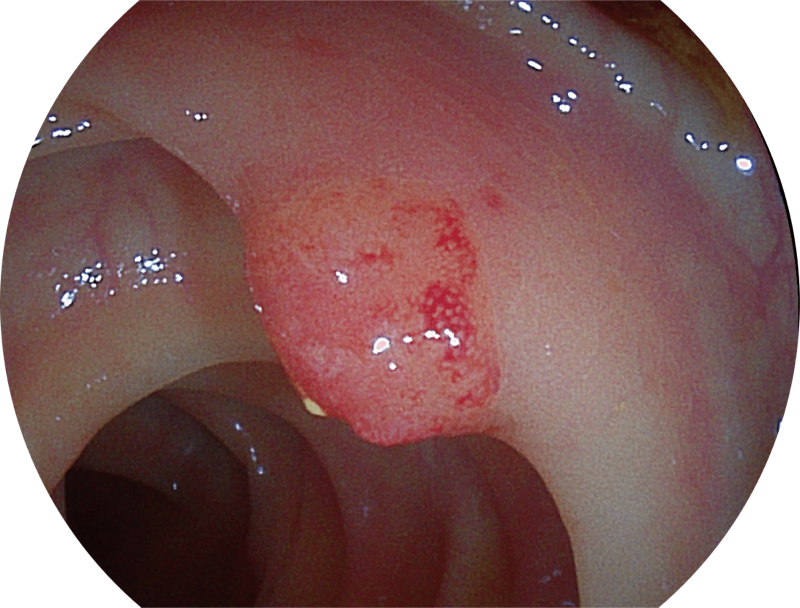

(Versatile Intelligent Staining Technology)

能够凸显黏膜浅层血管轮廓和黏膜表面微结构,适用于中、近景观察下的早癌精确诊断。